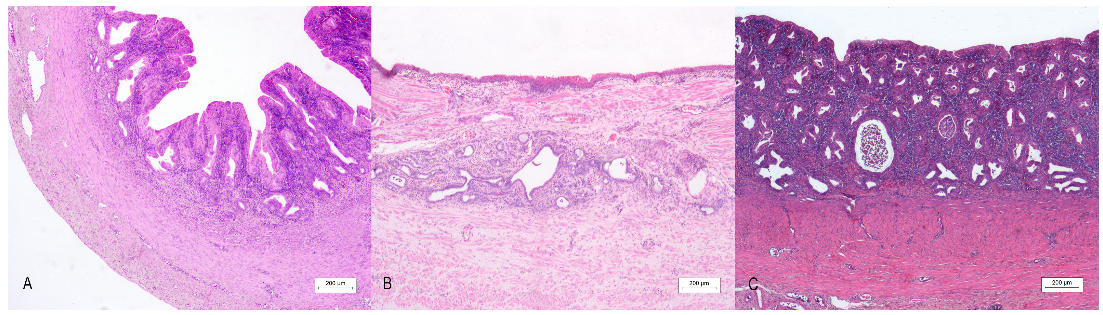

Histological features revealed the presence of a rudimental tubular structure with a three-layer appearance in all cases, resembling a uterine wall (Figure 3A). The innermost layer was composed of a simple columnar epithelium, with a multifocal microvacuolar cytoplasm and basal nucleus reminiscent of the progestinic change in the female uterus, supported by a moderate amount of fibrovascular stroma in cases 1 and 3. In case 3, luminal cells also exhibited an abrupt transition to a simple stratified epithelium, whereas in case 2, epithelial cells showed squamous metaplasia with multifocal keratinization (Figure 3C). Moderate lymphoplasmacytic and neutrophilic inflammation and numerous simple tubular glands filled with neutrophils and cellular debris were detected in all the cases (Figure 3B). The second layer consisted of densely packed smooth muscle cells resembling myometrium. An external thin layer of connective tissue represented the perimetrium. Histological evaluation from both testes of case 3 revealed the presence of an intratubular and invasive Sertoli cell tumor, while a testis of case 1 evidenced a normal testicular histology.

Figure 3.

Uterus masculinus, histological findings: (A) Case number 3: The wall of the uterus masculinus with a three-layer appearance. Bar 200 µm. (B) Case number 2: Longitudinal section of the mucosal wall with squamous epithelium. Bar 200 µm. (C) Case number 1: Moderate lymphoplasmacytic and neutrophilic inflammation of the mucosal layer of the canine uterus masculinus. (A–C): Under 4× magnification, bar 200 µm, hematoxylin–eosin stain.

By immunohistochemistry, AMH was expressed in the cytoplasm of tubular glands in all cases. In contrast, luminal epithelial cells (Figure 4) showed diffuse-strong cytoplasmic positivity only in case 1, while the other two cases displayed multifocal AMH expression.